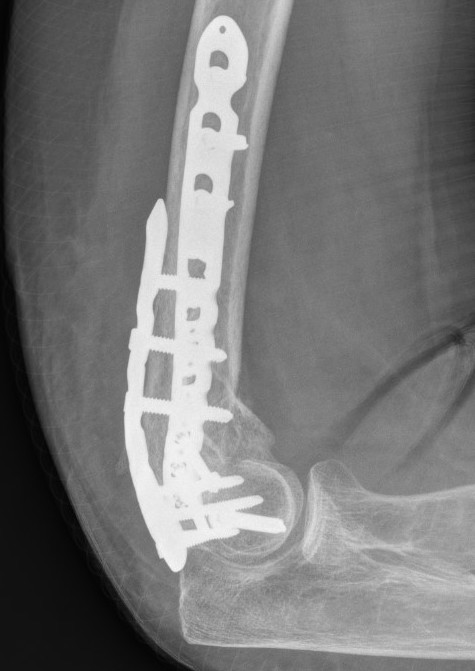

Fixation techniques

Options

Precontoured anatomical plates

Parallel plates v perpendicular plates

Locking v non locking screws

Parallel v perpendicular plates

Parallel plates - medial plate on medial column and lateral plate on lateral column

Perpendicular plates - plates at 90 degrees, with lateral plate posterior

- cadaveric model

- biomechanical superiority of parallel plates versus perpendicular plates

- systematic review of 83 studies and 2362 patients

- parallel plating lower incidence of revision for fixation failure (1% v 6%)

- perpendicular plating reduced overall complication (45% v 54%)

- these complications included lower incidence neuropathy, wound dehiscence, and implant prominence